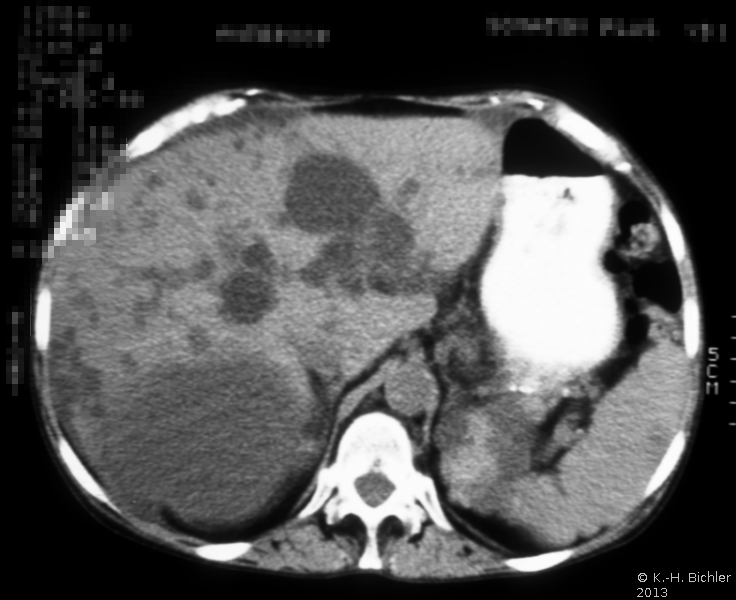

Die Diagnose wird mittels Anamnese (zystische Nierenerkrankungen in der Familie), RR-Messung, Labor (Kreatinin) mit genetischer Untersuchung, Sonographie, Computertomographie und gegebenfalls Kernspintomographie gestellt (Abbildung 4).